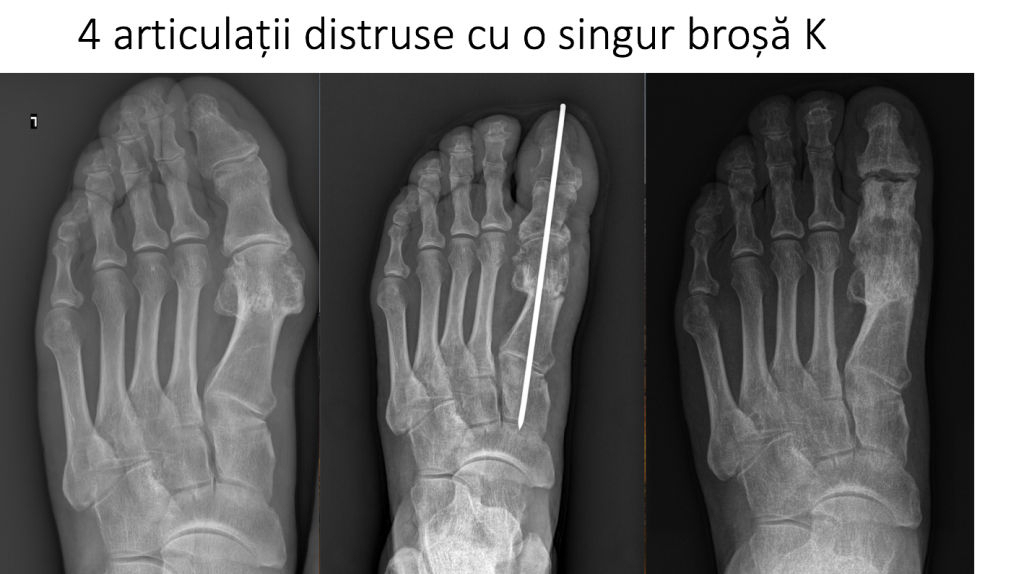

17. DISTRUGEREA ARTICULAȚIILOR ADIACENTE

- materialele de osteosinteza trebuie sa evite articulatiile;

- penetrarea articulatiilor cu brose metalice determina distrugerea rapida a acestora (artroza sau chiar blocarea articulatiilor).